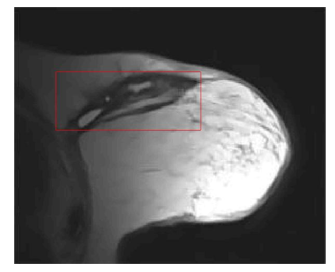

After several parameter adjustments, applying the DRLSE algorithm to this new medical image produced a less precise results in terms of segmenting the structures of interest. This observation prompted us to consider other approaches to improve segmentation quality. Figure 9 shows the segmentation result on breast MRI with α=1.5, λ=5, and μ=0.02.

a-Initial contour

b-Segmented image

Figure 9. Segmentation result with the DRLSE algorithm